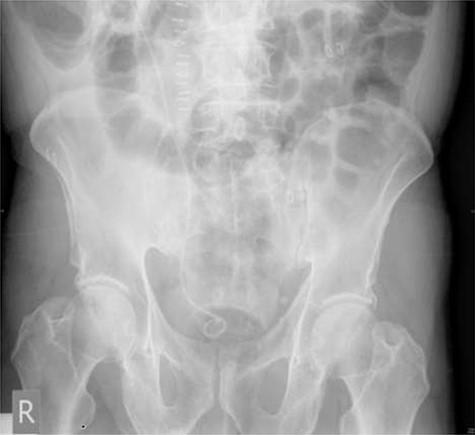

Following completion of chemotherapy, 12 weeks after stent insertion, the patient attended clinic for stent removal however, the stent could not be visualized on flexible cystoscopy. An abdominal X-ray showed proximal migration of the stent with the proximal end of the stent appearing to wrap around the aforementioned staghorn calculus (Fig. 4).

Plain abdominal X-ray performed at follow-up demonstrating proximal ureteric stent migration.